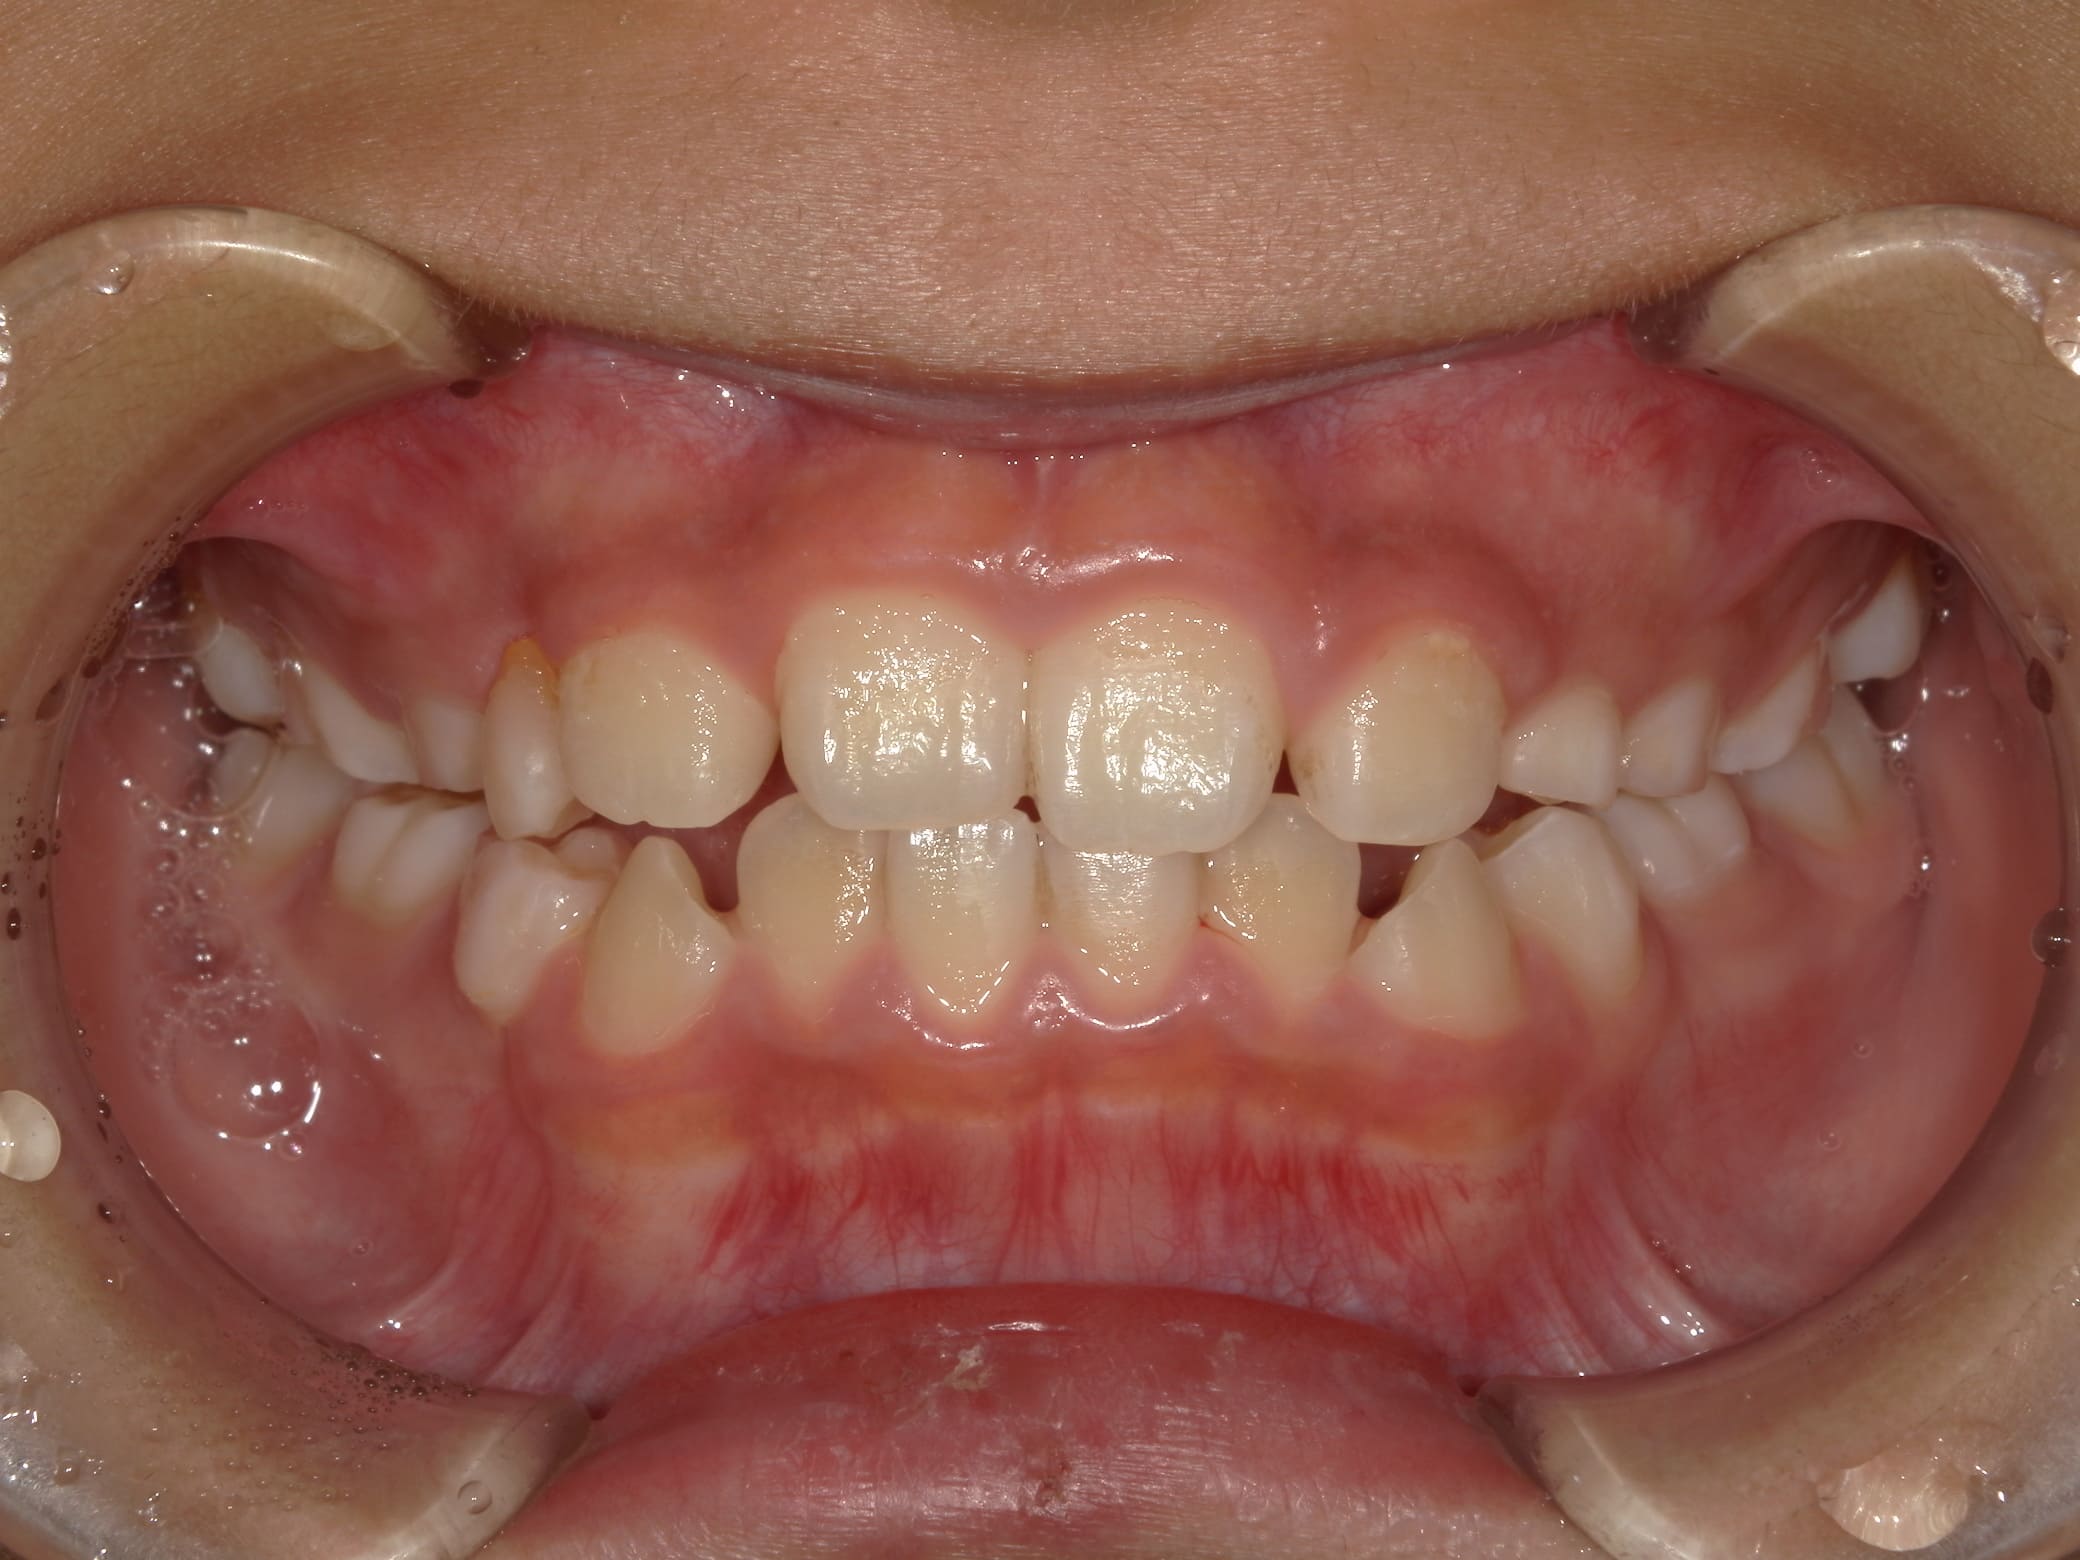

| 年齢・性別 | 7歳1ヶ月の男児 |

|---|---|

| 主訴 | 歯の生えるスペース不足が懸念され、歯列の乱れ(叢生)を整えるために来院された患者様です。 |

| 治療期間・回数 | 1年3ヶ月・11回 |

| 費用 | 420,000円(税別) |